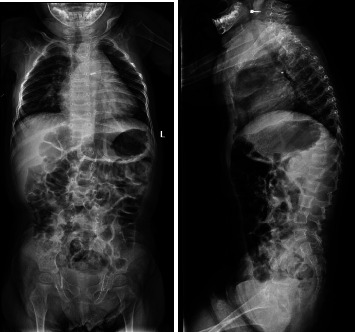

Geroderma Osteodysplastica (GO) is a rare autosomal recessive connective tissue disease characterized by wrinkled skin and osteoporosis, two distinct aging-related features. A loss of function mutation in GORAB results in the disease. Immediately after birth, a cyanotic female neonate was found to have transposition of great vessels (TGV) that was corrected with an uneventful surgical recovery. The patient was noted to have wrinkled skin and hyperlaxity in her joints. After a complete nutritional and metabolic panel, in addition to karyotyping, imaging, skin histopathology analysis, and genetic testing she was found to have GO. We found two novel compound heterozygous mutations in GORAB: p.Asp236∗ and pAsp236Ala. This is the first study that reports the concurrent incidence of GO with TGV. The patient was started on bisphosphonates, which led to a reduction in the occurrence of fractures. An early diagnosis of GO is warranted to prevent or reduce bone density loss due to osteoporosis via initiation of bisphosphonate treatment. Whole exome sequencing remains the gold standard for diagnosing GO and ruling out phenotypically similar disorders.

Abstract Image